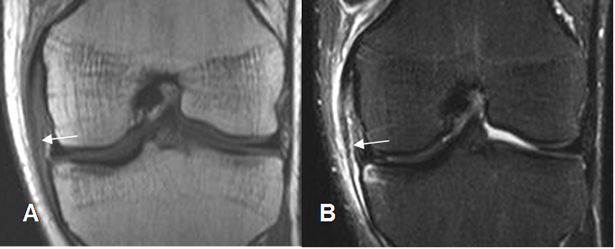

Fig 117 B. Esguince GI del LCM.

A: RM coronal en T1 y B: RM coronal en STIR. Cambios inflamatorios rodeando el LCM, el cual permanece íntegro, por esguince GI.

Fig 118. Esguince del LCM.

A: RM coronal en T1 y B: RM coronal en STIR. Alteración en la señal del LCM, el cual es hipointenso en T1 e hiperintenso en STIR, sin ruptura completa de sus fibras, por esguince G II.